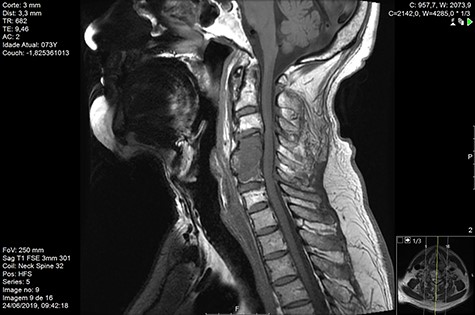

MRI and CT scans performed at 90 days post-radiation therapy showed an arrest of further progression of instability and resolution of the lytic lesion (Figs 7–13).